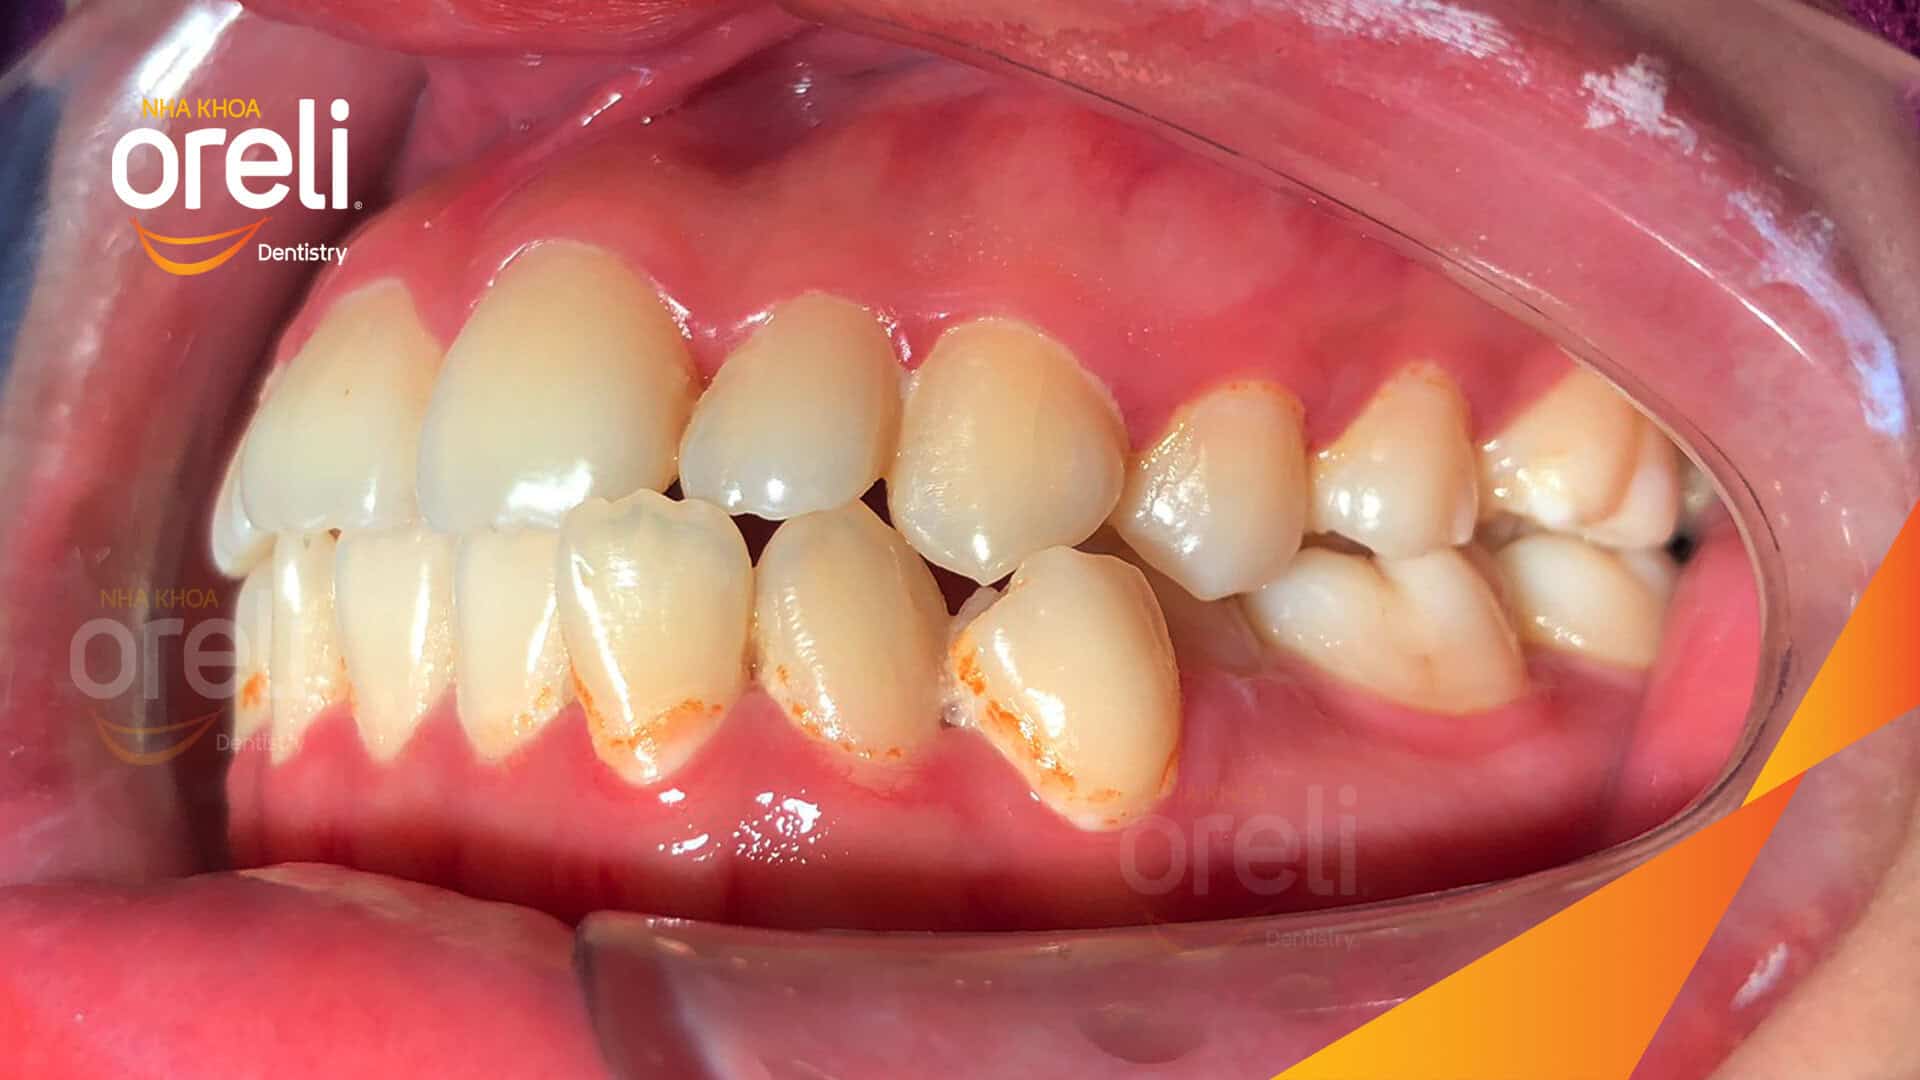

Hành trình thay đổi nụ cười ca lệch khớp cắn hạng 3, hàm dưới trượt ra trước và nhô xương hai hàm.

Tình trạng này không chỉ ảnh hưởng đến thẩm mỹ khuôn mặt mà còn gây khó khăn trong ăn nhai và phát âm. Thông qua quá trình niềng răng được cá nhân hóa, khách hàng đã từng bước cải thiện khớp cắn và lấy lại sự tự tin trong giao tiếp.